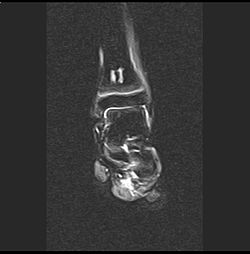

| Aseptische Knochennekrose - sagittale MRT (STIR-Sequenz) einer aseptischen Knochennekrose mit Befall der distalen Tibia bei einem 13-jährigen Kind mit akuter lymphatischer Leukämie (ALL) . | Eigenes Werk | Christaras A | Datei:AON distal tibia - MR STIR coronal - 13 yr child with ALL.jpg | |